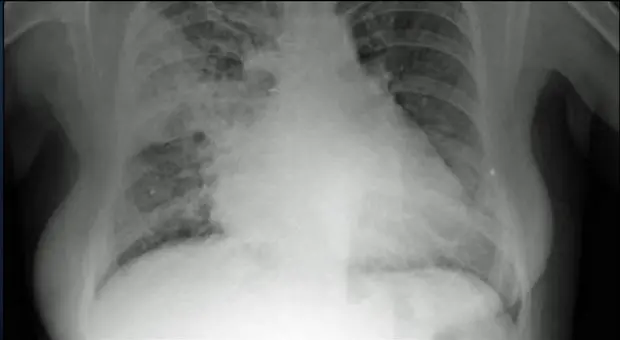

Secondo uno studio pubblicato su Nature, le persone che hanno contratto il Coronavirus, già a 30 giorni dalla malattia e fino ad un anno dalla guarigione, hanno un aumentato rischio di sviluppare problemi al cuore

Una donna prossima al parto è risultata positiva ad entrambi i virus. Non è un nome scientifico: i medici hanno ribattezzato così l'infezione simultanea al Covid e all'influenza